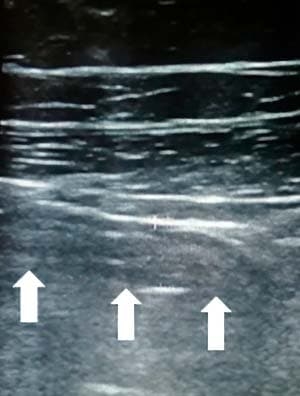

В воспаленном аппендиксе перистальтика отсутствует, и это заметно выделяется на фоне перистальтирующих нормальных петель кишечника (см. рис. 5).

Рисунок 5. Отсутствие перистальтики в воспаленном аппендиксе.